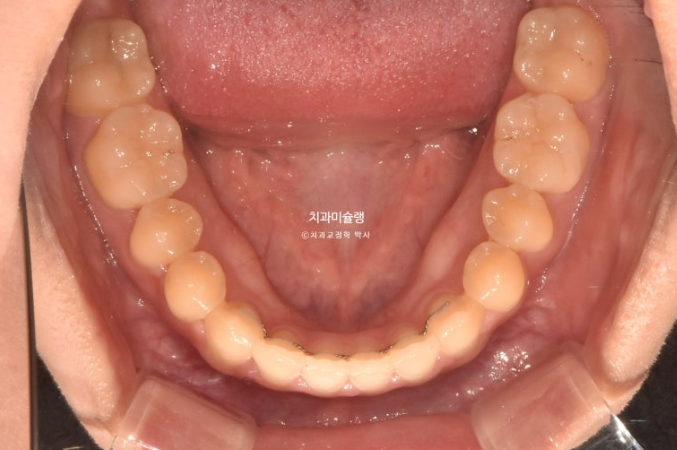

어릴때 교정을 했었고 아래턱이 자라 앞니가 거꾸로 물리게 되었습니다.

측방치군, 즉 송곳니와 작은어금니에 개방교합이 보입니다.

아래 앞니가 위 앞니보다 앞에 물려 거꾸로 물림, 반대교합이 보입니다.

아래 매복 사랑니가 있어서 사랑니를 발치하고 사랑니 공간으로 아래 전체치열을 뒤로 미는 교정이 필요합니다.